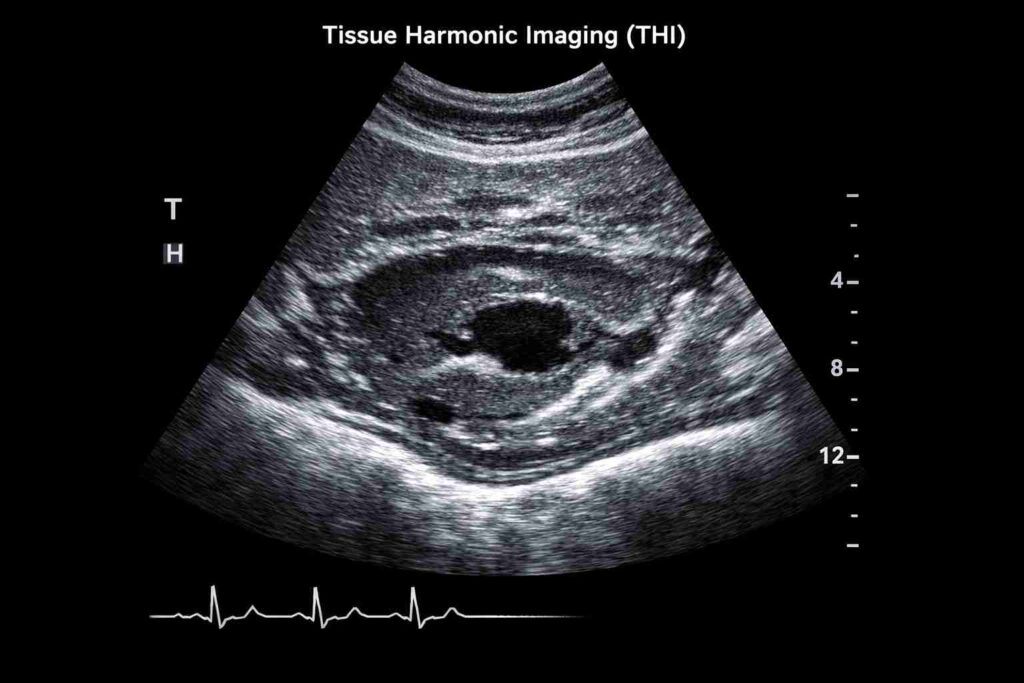

Tissue Harmonic Imaging (THI)

Tissue harmonic imaging, also known as native harmonic imaging, is a signal processing technique used in ultrasound. During the transmit phase of the pulse-echo cycle, an ultrasound beam insonates body tissues, generating harmonic waves due to nonlinear distortion. These harmonic waves are then utilised to enhance image quality and improve diagnostic accuracy. (SOURCE)

- Reduced Haze: Clears the “fog” in fluid-filled areas, such as the bladder.

- Sharper Borders: Makes the edges of organs or tumours stand out clearly.

- Deep Penetration: Maintains clarity even when looking at deep-seated structures.